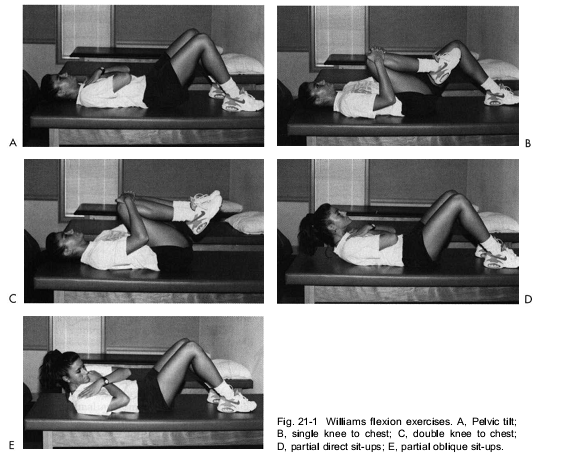

- Chương trình tập Williams.

Chương trình tập Williams chủ yếu dựa trên các tư thế gập, được dùng để điều trị cho bệnh nhân lớn tuổi, thoái hóa.

Xem bài: Chương trình tập luyện Williams